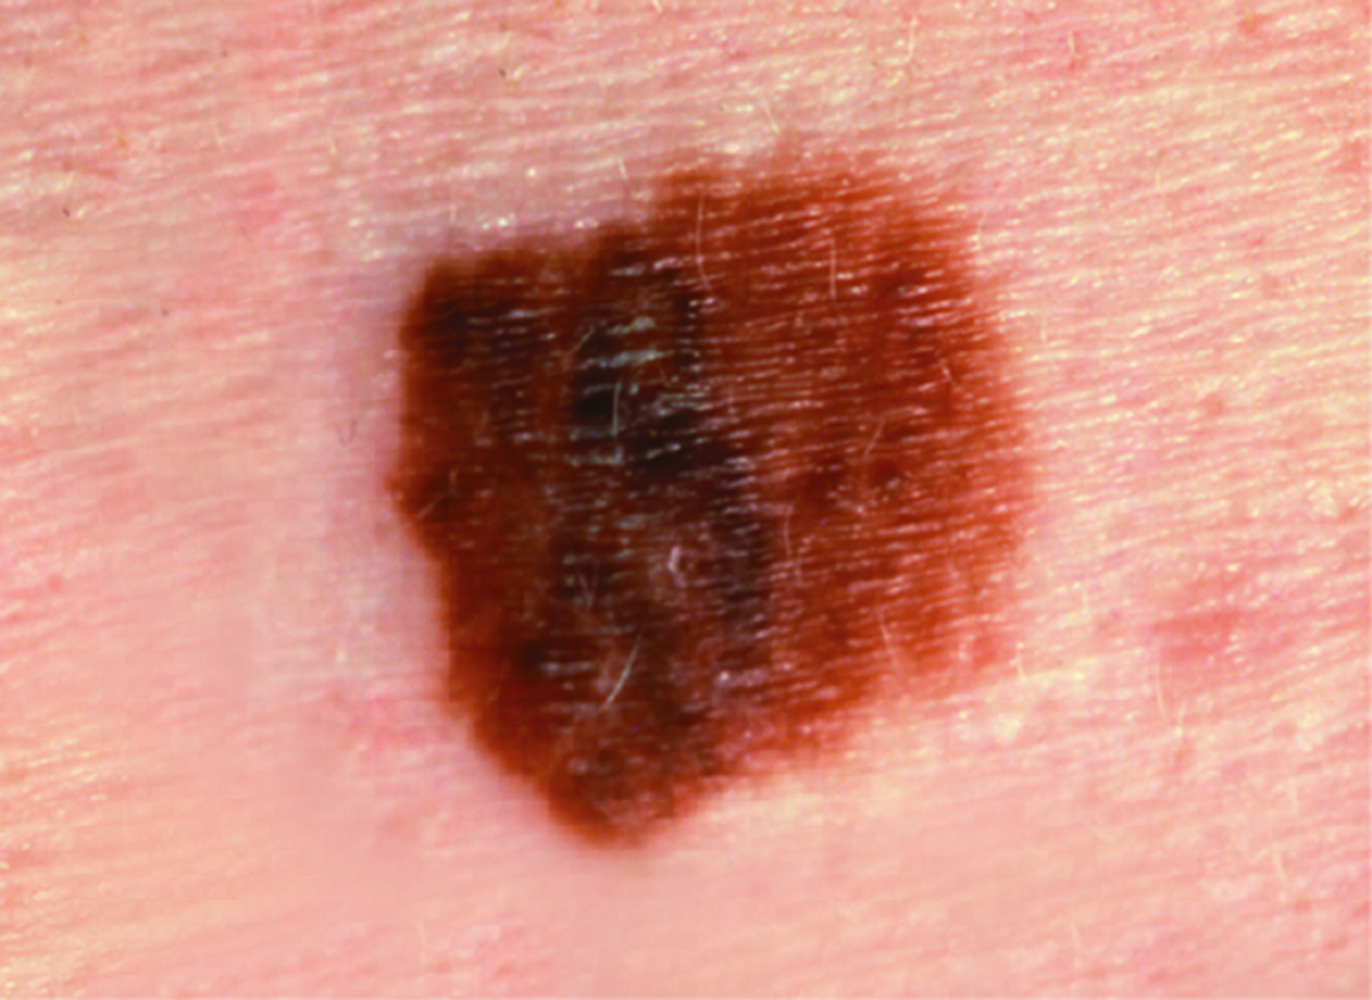

Melanoma Photos

Nodular melanoma on the leg of a Native American woman.

Photo: International Skin Imaging Collaboration

Amelanotic melanomas may be pinkish-looking, reddish, purple, normal skin color or essentially clear and colorless.